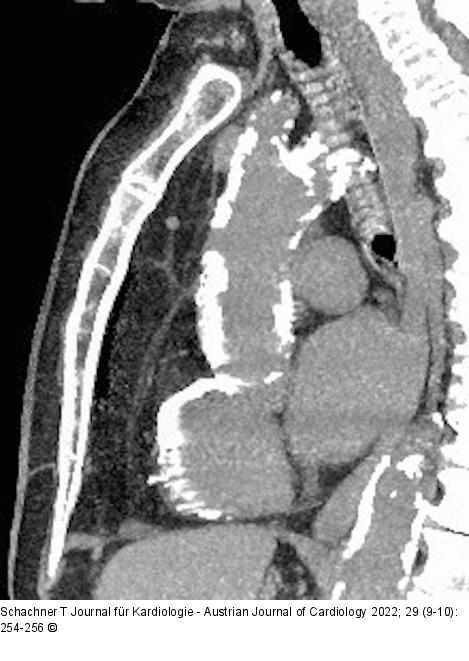

Abbildung 2: Aorta Schwerste Verkalkung der gesamten Aorta bei Patientin mit komplexer koronarer Dreigefäßerkrankung. |

Schwerste Verkalkung der gesamten Aorta bei Patientin mit komplexer koronarer Dreigefäßerkrankung. |